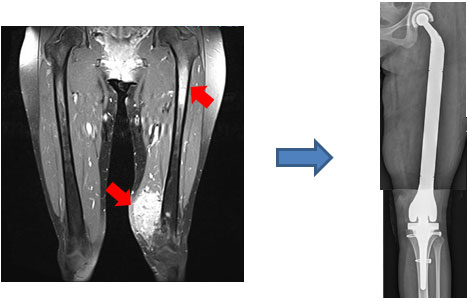

大腿部胞巣状軟部肉腫で大腿骨にも転移を認めた症例

腫瘍および大腿骨を切除し大腿骨全置換術を施行